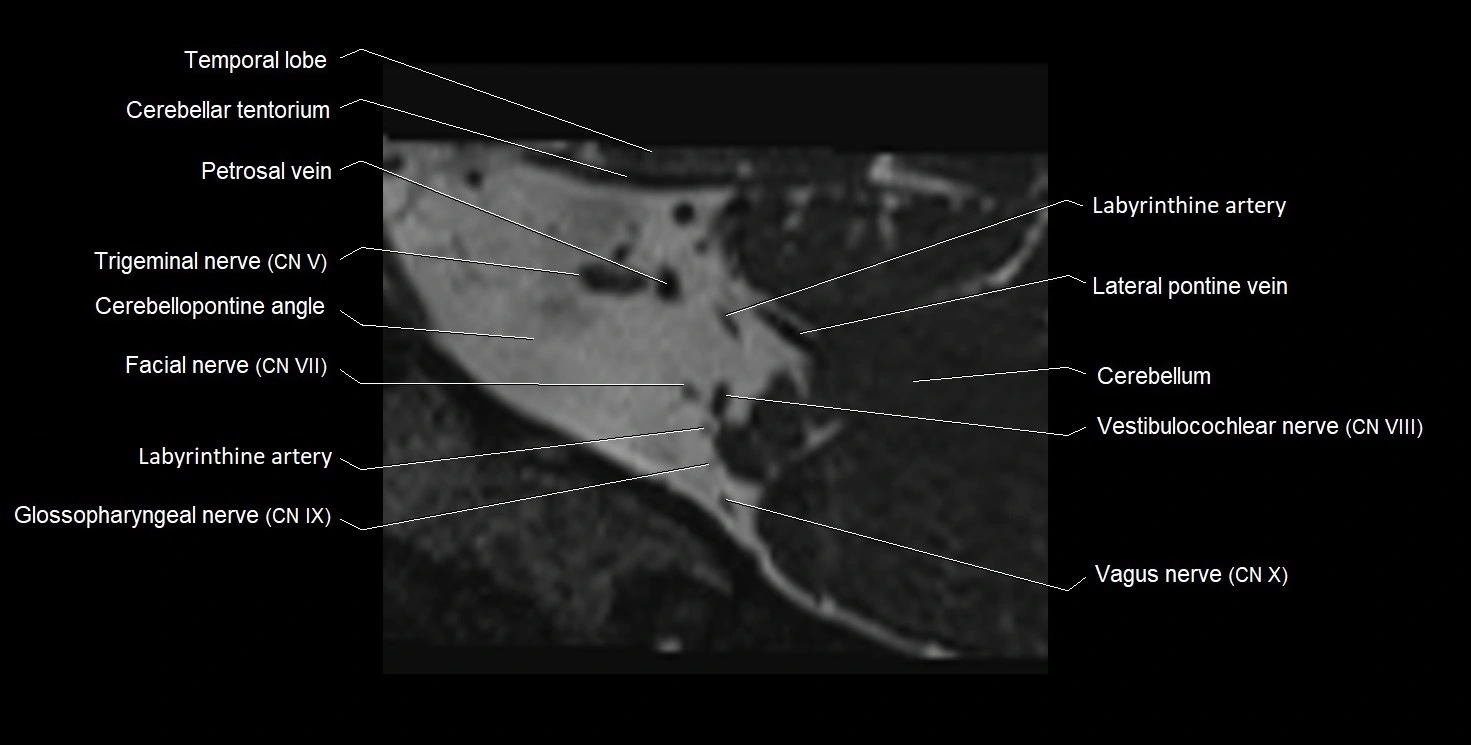

MRI Appearance

• The abducens nerve is a small, thin, linear structure

• Best visualized on high-resolution T2-weighted 3D MRI sequences (e.g., FIESTA or CISS)

• Seen as a hypointense (dark) line running from the brainstem at the pontomedullary junction, traversing the prepontine cistern, and entering Dorello’s canal under the petrosphenoidal ligament, then into the cavernous sinus, and finally the orbit

• May be challenging to visualize in standard MRI due to its small size

• Pathology may be inferred by absence, displacement, or enhancement of the nerve